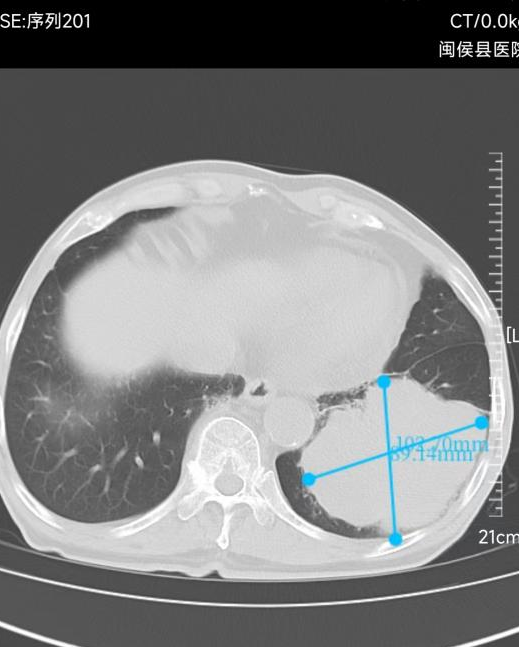

10cm肺部肿瘤

手术当天,徐驯宇主任及其名医工作室成员黄郴副主任医师与当地医院外科、手术室的同事共同努力,克服了患者肿瘤巨大,胸腔黏连严重的困难,为江老伯实施了胸腔镜下左下肺叶切除手术。整个手术耗时4个半小时,出血约200ml。